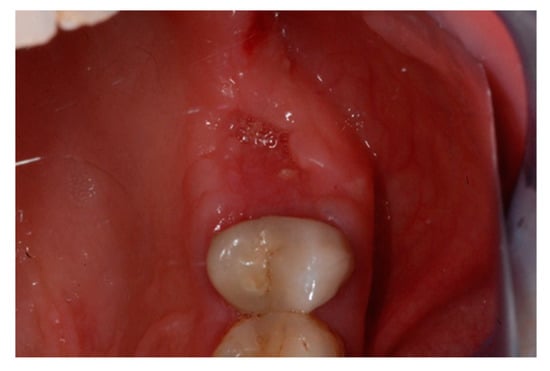

Ten days after the extraction and socket preservation, the patient was recalled for the suture removal. The clinical observation showed the occurrence of physiological healing without any complication (Figure 6 and Figure 7).

Figure 6.

Vestibular intraoperative view of the oral mucosa 10 days after tooth extraction and socket preservation. Soft tissues appeared completely healed with no signs of bone exposition, considered as a clear sign of bisphosphonate-related osteonecrosis of the jaw (BRONJ).